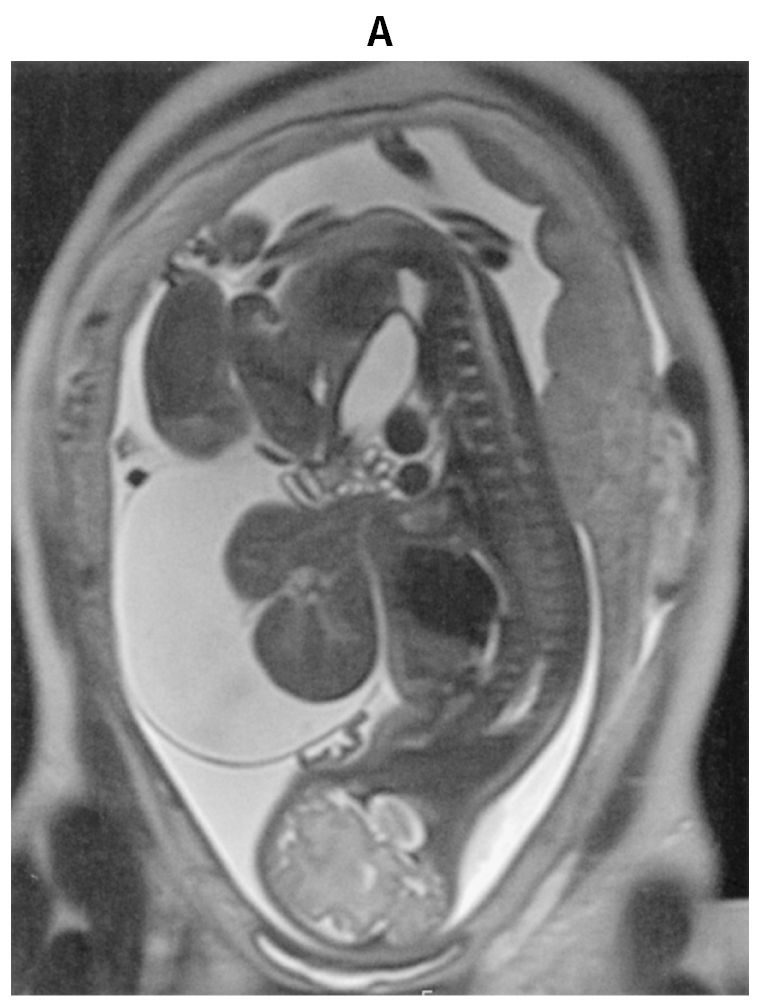

32歳の初妊婦(1妊0産)。妊娠20週時に胎児超音波検査で体外に臓器が脱出している所見を認めた。精査のために妊娠32週時に撮影した胎児単純MRIのT2強調矢状断像(A)(B)を下に示す。